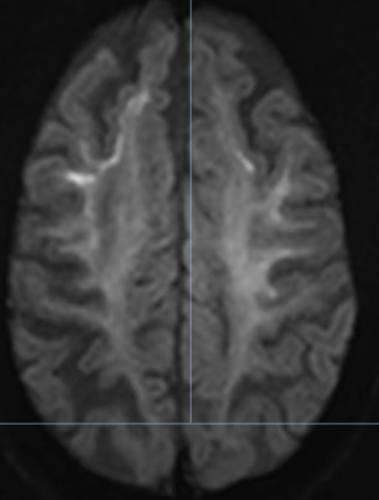

张伯的颅脑核磁平扫表现出了与之年龄很不匹配的脑萎缩,尤其是在弥散成像上呈现出脑梗死的高信号表现。

不同于脑梗死,张伯的弥散成像高信号改变有特征性——是分布于额顶叶皮层与白质交界区线样高信号。